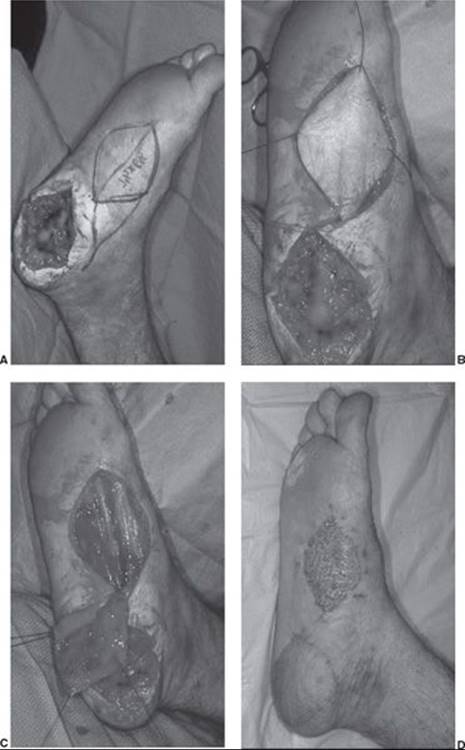

FIGURE 95.9. Medial plantar flap. The most versatile fasciocutaneous flap of the foot is the medial plantar flap. It is ideal for the coverage of plantar defects. It can be harvested on the superficial medial plantar artery or on the deep medial plantar artery. The flap shown is based on the deep medial plantar artery. A) The patient has a melanoma resected from his plantar heel. The medial plantar flap is drawn out on the plantar instep over the medial plantar artery. B) The medial plantar flap is dissected off of the instep. C) The medial plantar flap is elevated off of the instep. D) The healed wound shows a healed flap covering the plantar heel and the instep skin grafted.

The most versatile fasciocutaneous flap of the foot is the medial plantar flap, which is the ideal tissue for the coverage of plantar defects. It can also reach medial ankle defects. The flap can be harvested to a size as large as 6 cm × 10 cm, has sensibility, and has a wide arc of rotation if it is taken with the proximal part of the medial plantar artery whether distally based on the superficial medial plantar artery or on the deep medial plantar artery (Figure 95.9). Although easier to harvest on the deep medial plantar branch, it is preferable to harvest the flap based on the superficial branch because there is less disturbance of the inflow to the remaining foot. When harvested with retrograde flow, the flap should be based on the deep branch of the medial plantar artery.